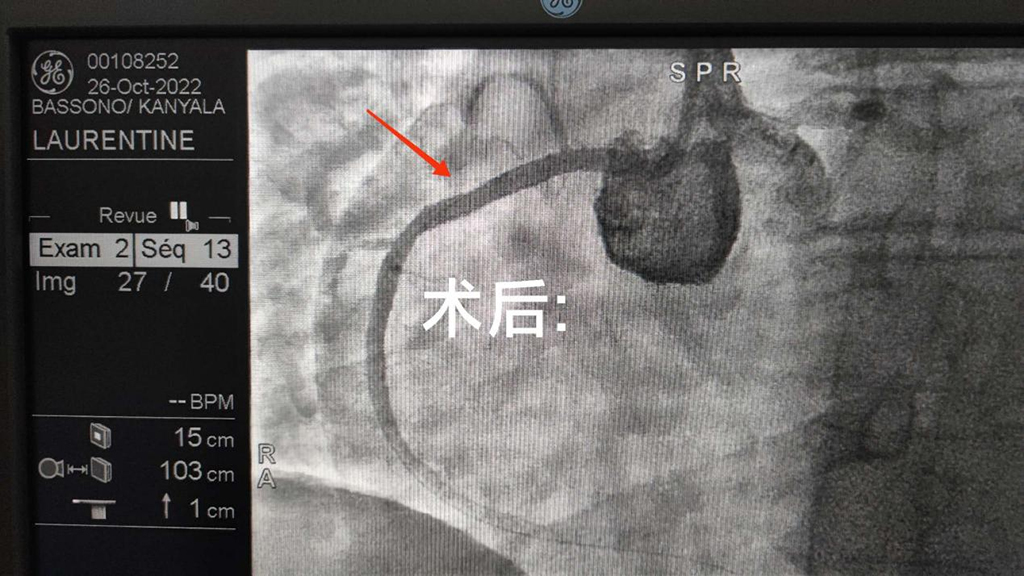

另一位患者行冠脉造影提示:右冠状动脉狭窄90%,于右冠状动脉植入一枚支架,术后患者胸闷明显好转,从之前的活动后胸闷到现在可以走很远的路,这其间有着我们的全身心投入。正是因为坚守着尽自己最大的努力帮助每一位患者的初衷,才使布基纳法索人民能够享受到良好的医疗。术后患者脸上的笑容,是对我们的最大肯定,一句布式中文的“谢谢”,是对中国医生最好的信任。